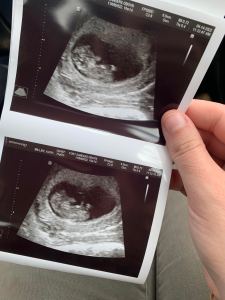

If you came here for the ultrasound pics, I promise I won’t disappoint! We’ve had a few ultrasounds already, so here are our favorite images from our 8 week, 10 week, and 12 week ultrasounds.